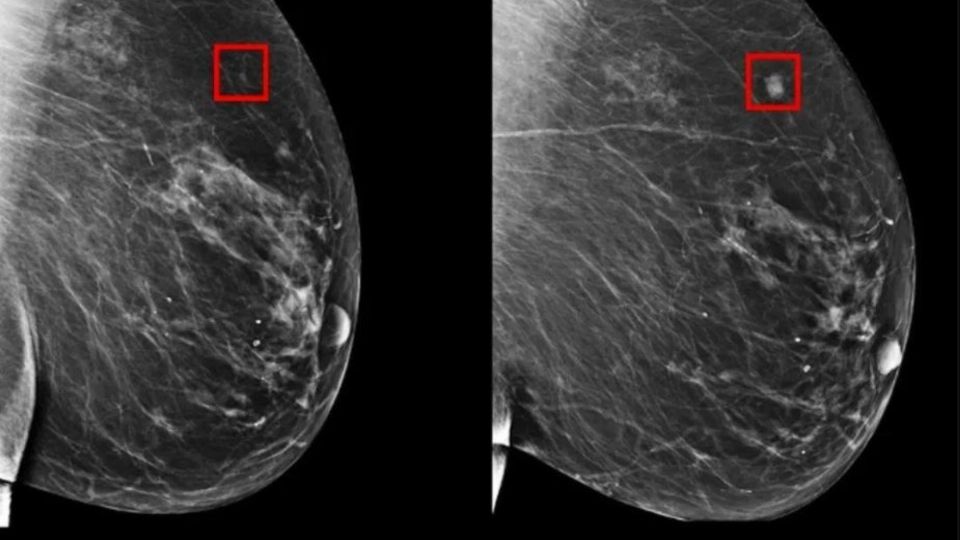

Imagen generada por IA en que se aprecia la aparición de un tumor cancerosoCréditos: Tw/@digitalcerebro

Dicho sistema de Inteligencia Artificial ha demostrado ser particularmente eficiente al identificar señales delicadas en los tejidos mamarios que suelen pasar desapercibidas en las revisiones llevadas a cabo por los especialistas, lo que le permite estimar en un alto porcentaje la probabilidad de que una paciente desarrolle cáncer.